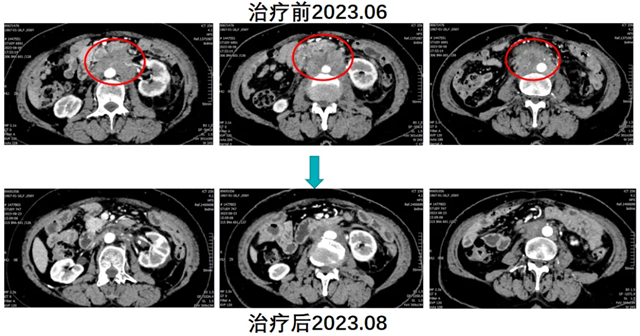

林女士因“腹痛”就诊内江市第二人民医院肿瘤四科(头颈盆腔食管肿瘤科),完善检查后诊断为子宫内膜样腺癌术后腹腔及盆腔多发淋巴结转移。结合患者临床表现、病史及影像学检查,考虑患者肿瘤进展、瘤负荷大、贫血重,且对传统免疫联合化疗无效,腹痛症状给生活质量带来严重影响。

经肿瘤四科(头颈盆腔食管肿瘤科)团队充分讨论,建议患者行腹主动脉旁淋巴结空间分割放疗联合免疫治疗(卡瑞利珠单抗)及生物治疗(人粒细胞巨噬细胞刺激因子)。与患者及家属沟通病情并经同意后,实施了上述治疗方案。放疗后患者返院高兴的讲述道腹部疼痛已经没有了,复查CT显示腹腔淋巴结明显缩小,治疗效果显著,续继免疫维持治疗。患者肿瘤持续缩小、生活质量明显提高,今年8月复查显示肿瘤基本消失。

患者就诊时已属于晚期子宫内膜癌,且对免疫联合化疗耐药,可选择治疗手段非常有限。患者如果不尝试“鸡尾酒”(空间分割放疗联合免疫及生物治疗)式疗法,预计生存时间不超过半年。通过“鸡尾酒”疗法成功逆转了免疫耐药,极大地延长了患者的生存时间,明显提升了患者的生存质量。